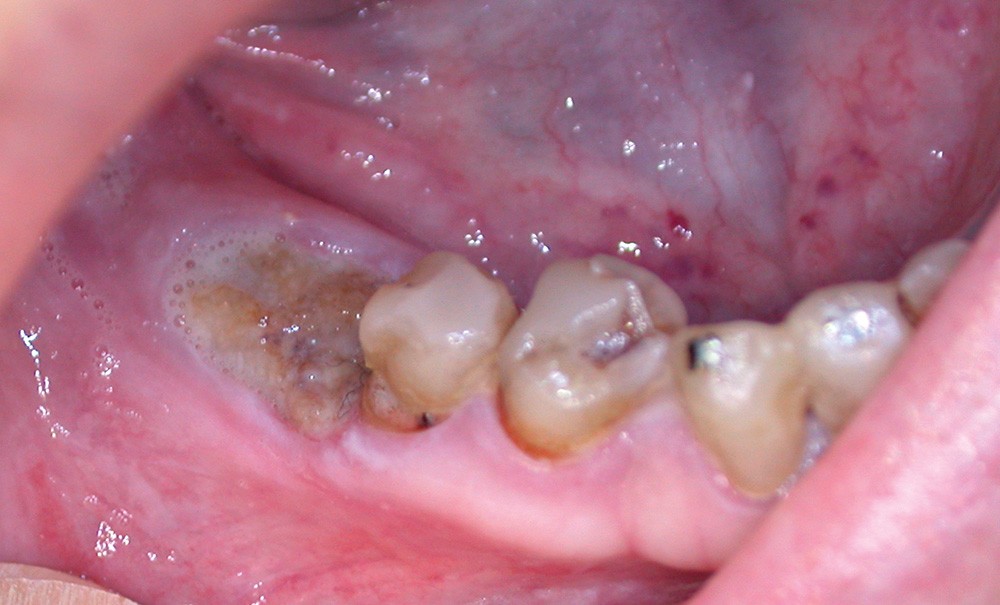

Un contrôle à la fréquence de 4 à 6 mois devra être instauré. La fréquence sera adaptée à l’état bucco-dentaire et à l’appréciation des facteurs locaux de susceptibilité du patient (risque carieux, biotype parodontal). La motivation à l’hygiène et l’efficacité du contrôle de plaque devront être entretenues. Les soins conservateurs précoces seront bien entendu privilégiés. Dans ce contexte, il ne faudra pas hésiter à conserver des dents d’une valeur intrinsèque faible pour éviter le recours à un geste chirurgical. En cas de carie délabrante ou de mobilité modérée, les soins conservateurs devront être privilégiés (endodontie, contentions). En cas d’infection, un traitement conservateur devra également être envisagé (fig. 2).